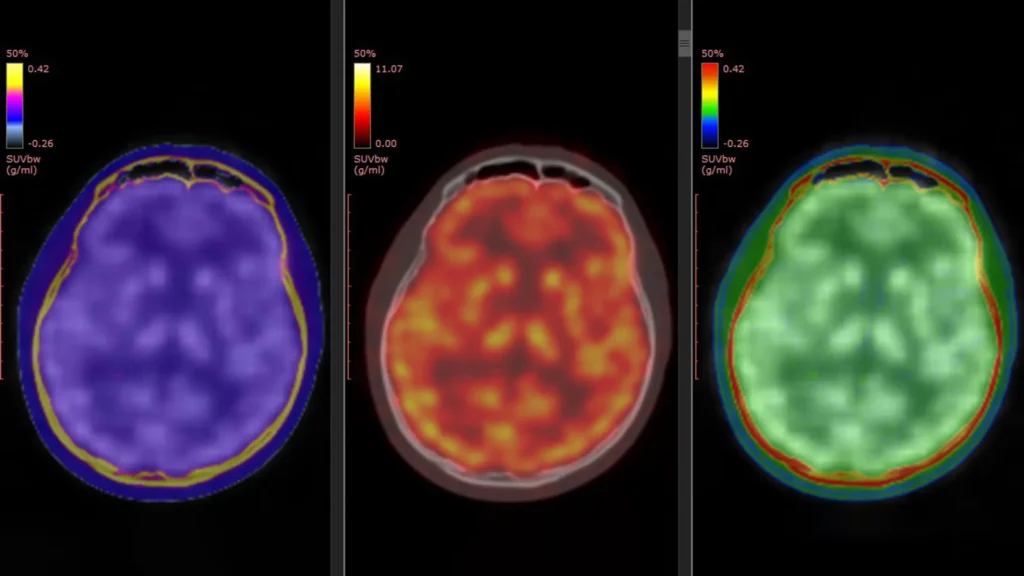

Parkinson’s illness is a long run neurological situation that steadily worsens through the years. A couple of million other people in the USA live with the dysfunction, and about 90,000 new instances are recognized each and every 12 months. Present medicines and treatments can ease signs, however no remedy has been confirmed to prevent or […]